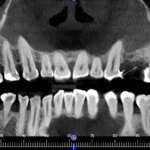

Radiologia in endodonzia: come migliorare la terapia Premium

La diagnosi e la terapia in endodonzia non possono prescindere dall’esecuzione di esami radiologici di alta qualità: la radiologia, infatti, permette di valutare lo...